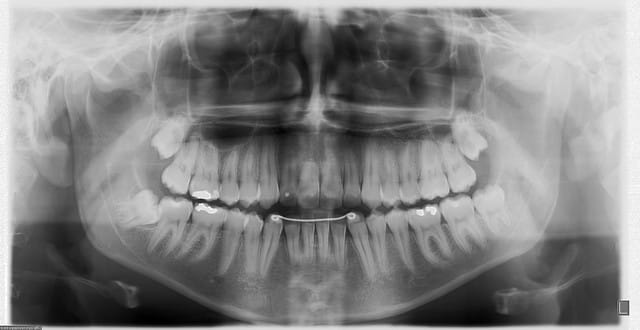

14 ans. C'est moi qui m'y colle mi-mai (dégagement chirurgical des couronnes et traction orthodontique).

Le haut, c'est banal.

Par contre pour le bas, c'est une autre histoire... Je ne vois pas d'autre solution que des ancrages osseux latéraux pour y arriver sans télescoper les racines des incisives. Haut les coeurs ! On y arrivera !

En pièces jointes, les radios de contrôle faites à 11h45. Je n’ai pas encore eu le temps de traiter les photos.

Un système que je développe moi-même depuis quelques années et qui a des possibilités d’évolution qui semblent infinies (Rev Orthop Dento Faciale 2006;40:63-90). Ici, j’ai utilisé deux vis de chirurgie maxillo-faciale en tandem sous muqueuses. Y est accroché un fil en TMA .018 qui émerge en latéral le long du vestibule et vient tracter, comme une « canne à pêche » la ligature qui est collée directement aux couronnes des canines incluses.

En haut, système plus banal (si j’ose dire).

Oui, au cabinet sous anesthésie locale. D’abord le haut, puis le bas.

Difficile à dire, cela m’étonnerait quand même que cela puisse être inférieur à 18 mois compte tenu de la position de la 33. Dès que les incisives inférieures seront dégagées, j’attaquerai le traitement orthodontique proprement dit.

Seules différences : dans ce cas-ci j’ai quand même donné en final une couverture antibio, il y avait deux vis en tandem au lieu d’une et la canne à pêche ressemblait plutôt à cela (voir photo).